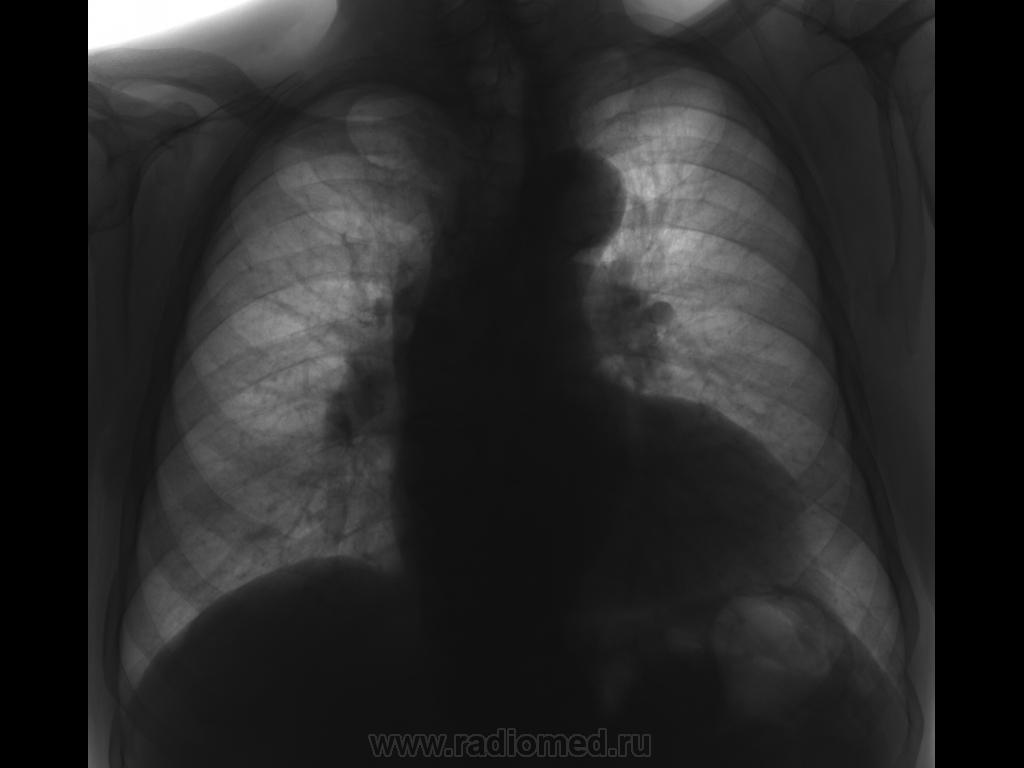

Пациент 1929 г. р. Случайная находка. Без жалоб. Архива нет. Крупная тень на позвоночнике в заднем средостении. Образование, настолько уплотненные стенки аорты накладиваются на выраженно дистрофически измененый позвоночник, аневризма.....?

Ваше мнение коллеги.

Аорта с аневризмой.

Склерозированная аорта без аневризмы.

Склерозированная аорта.

Я бы проверил пульсацию за экраном

Именно это я и хотел. Но пациент не возвращается для дообследования.